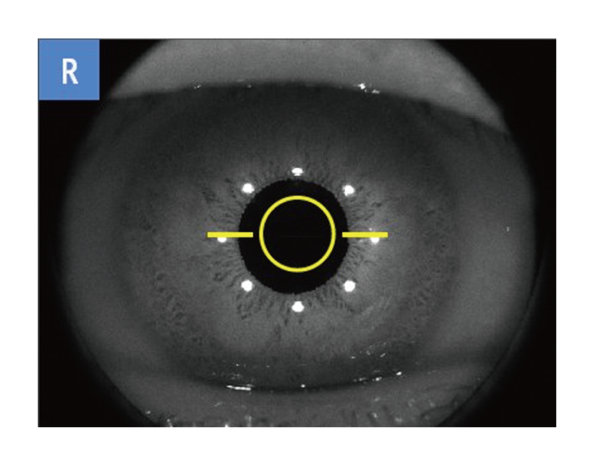

前眼部3Dオートアライメント機構

角膜輝点を検知するオートトラッキング機能を採用し、安定した撮影位置の追従を実現しました。

ジョイスティックを使わずマウスで簡単にアライメント操作が可能です。